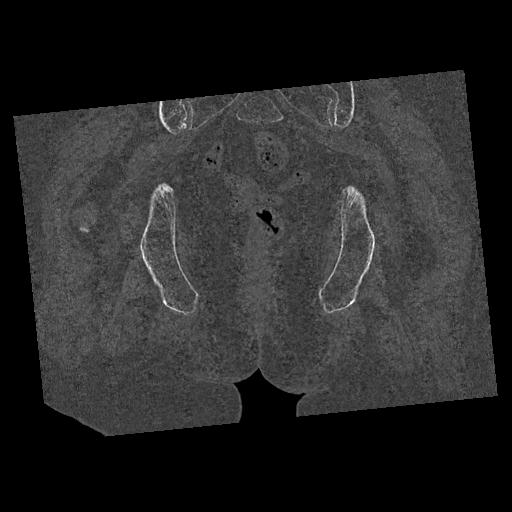

100703 1/27 両股正面+軸 1/29 両股正面+軸 94歳女性 パンソンロン